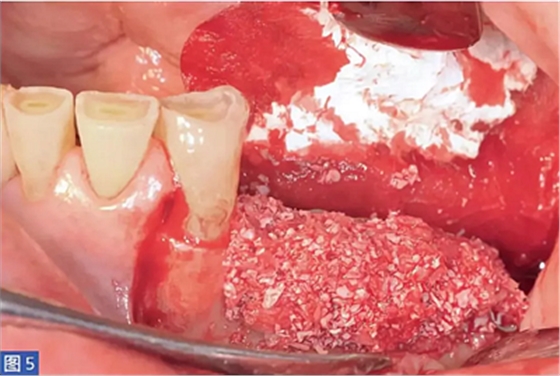

圖5:病例1. 在內(nèi)固定板限定空間中填塞移植物材料。